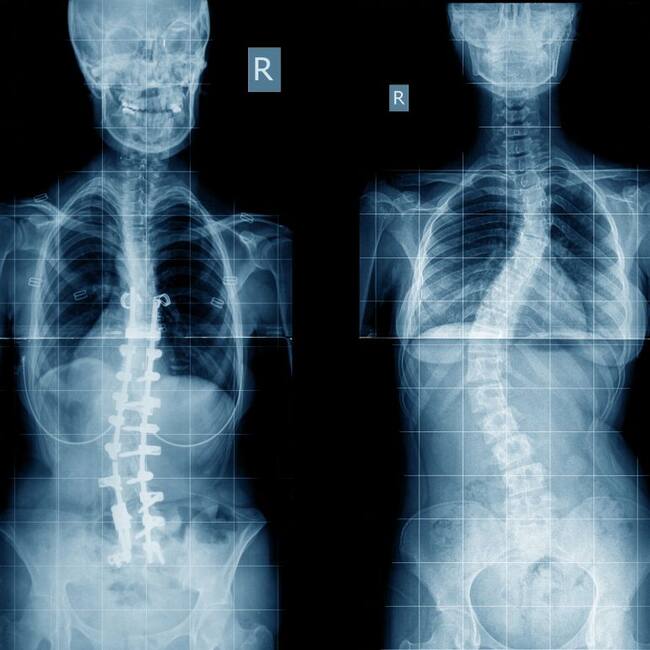

En nuestra sección de fisioterapia abordamos la escoliosis, una curvatura de nuestra columna que puede producirse a cualquier edad y cuyo origen, aún hoy, es desconocido.